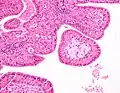

The appearance of this tumor under the microscope is unique. There are cystic spaces surrounded by two uniform rows of oncocytes, which are epithelial cells with abundant, granular, eosinophilic cytoplasm.[6] The cystic spaces have epithelium referred to as papillary infoldings that protrude into them. Additionally, the epithelium has lymphoid stroma with germinal center formation.

Low magnification micrograph of a Warthin tumor arising from the parotid gland.

Histopathology of Warthin tumor in the parotid gland. H&E stain.